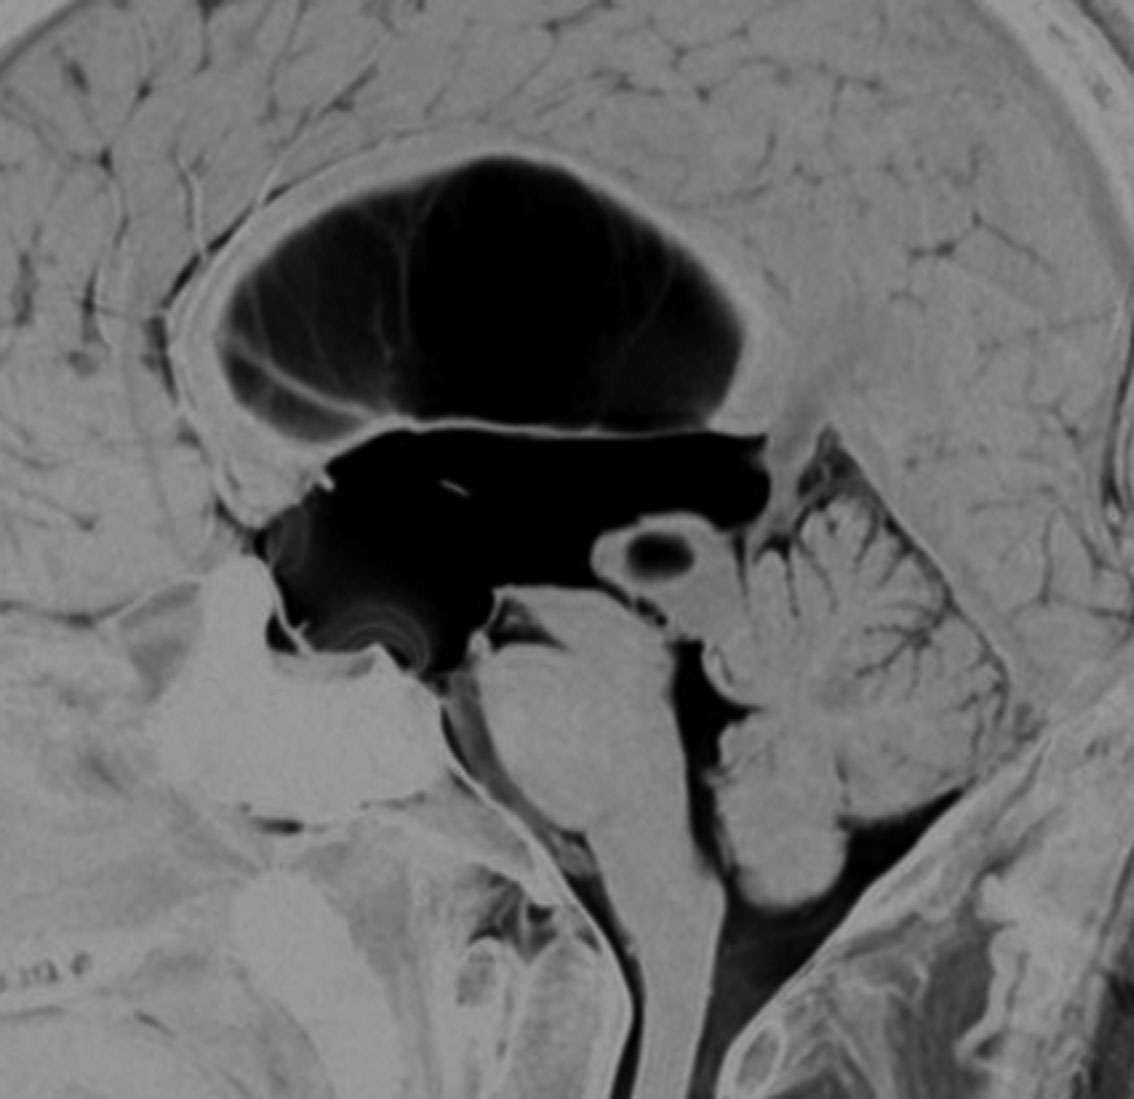

頭部打撲で検査され偶然発見された19歳男性ものです。中脳視蓋全体が腫大して腫瘍化しています。左側にのう胞があり周囲が淡くガドリニウムで増強されます。

中脳水道の癒着閉塞により,高度の停止性水頭症になっています。高身長ですが頭囲が61cmありました。小さい頃から頭が大きいので家族も気にならないようです。数年以上あるいは10年近くの長期にわたってこの水頭症は変わらないのでしょう。

頭痛などの症状はなく,眼底所見も視神経乳頭の異常はありませんでした。無治療で経過観察をしています。認知機能も全く正常で,国立大学から大学院に進む予定です。